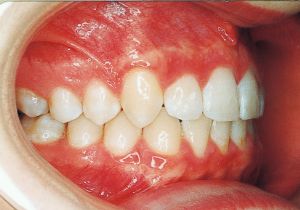

2 After Treatment 6-24-’95

4 After Treatment 6-24-’95 3 years and 7 months after starting treatment

5 After Retention 5 years and 6 months after starting treatment

Class II deep bite in mixed dentition. A significantly large overjet and a spaced arch are observed. The cephalometric X-ray shows that the anteroposterior displacement of the maxilla and mandible is not particularly large (ANB 5°), but the nasal floor is elevated anteriorly, providing evidence supporting a history of thumb sucking. The skeletal form shows a relatively slight mandibular body deficiency, but the mandibular ramus is adequately sized and appears likely to develop sufficiently. The use of headgear was planned to suppress maxillary anterior growth and achieve relative mandibular advancement. Treatment was performed without extraction, assuming continuity until the permanent dentition stage.